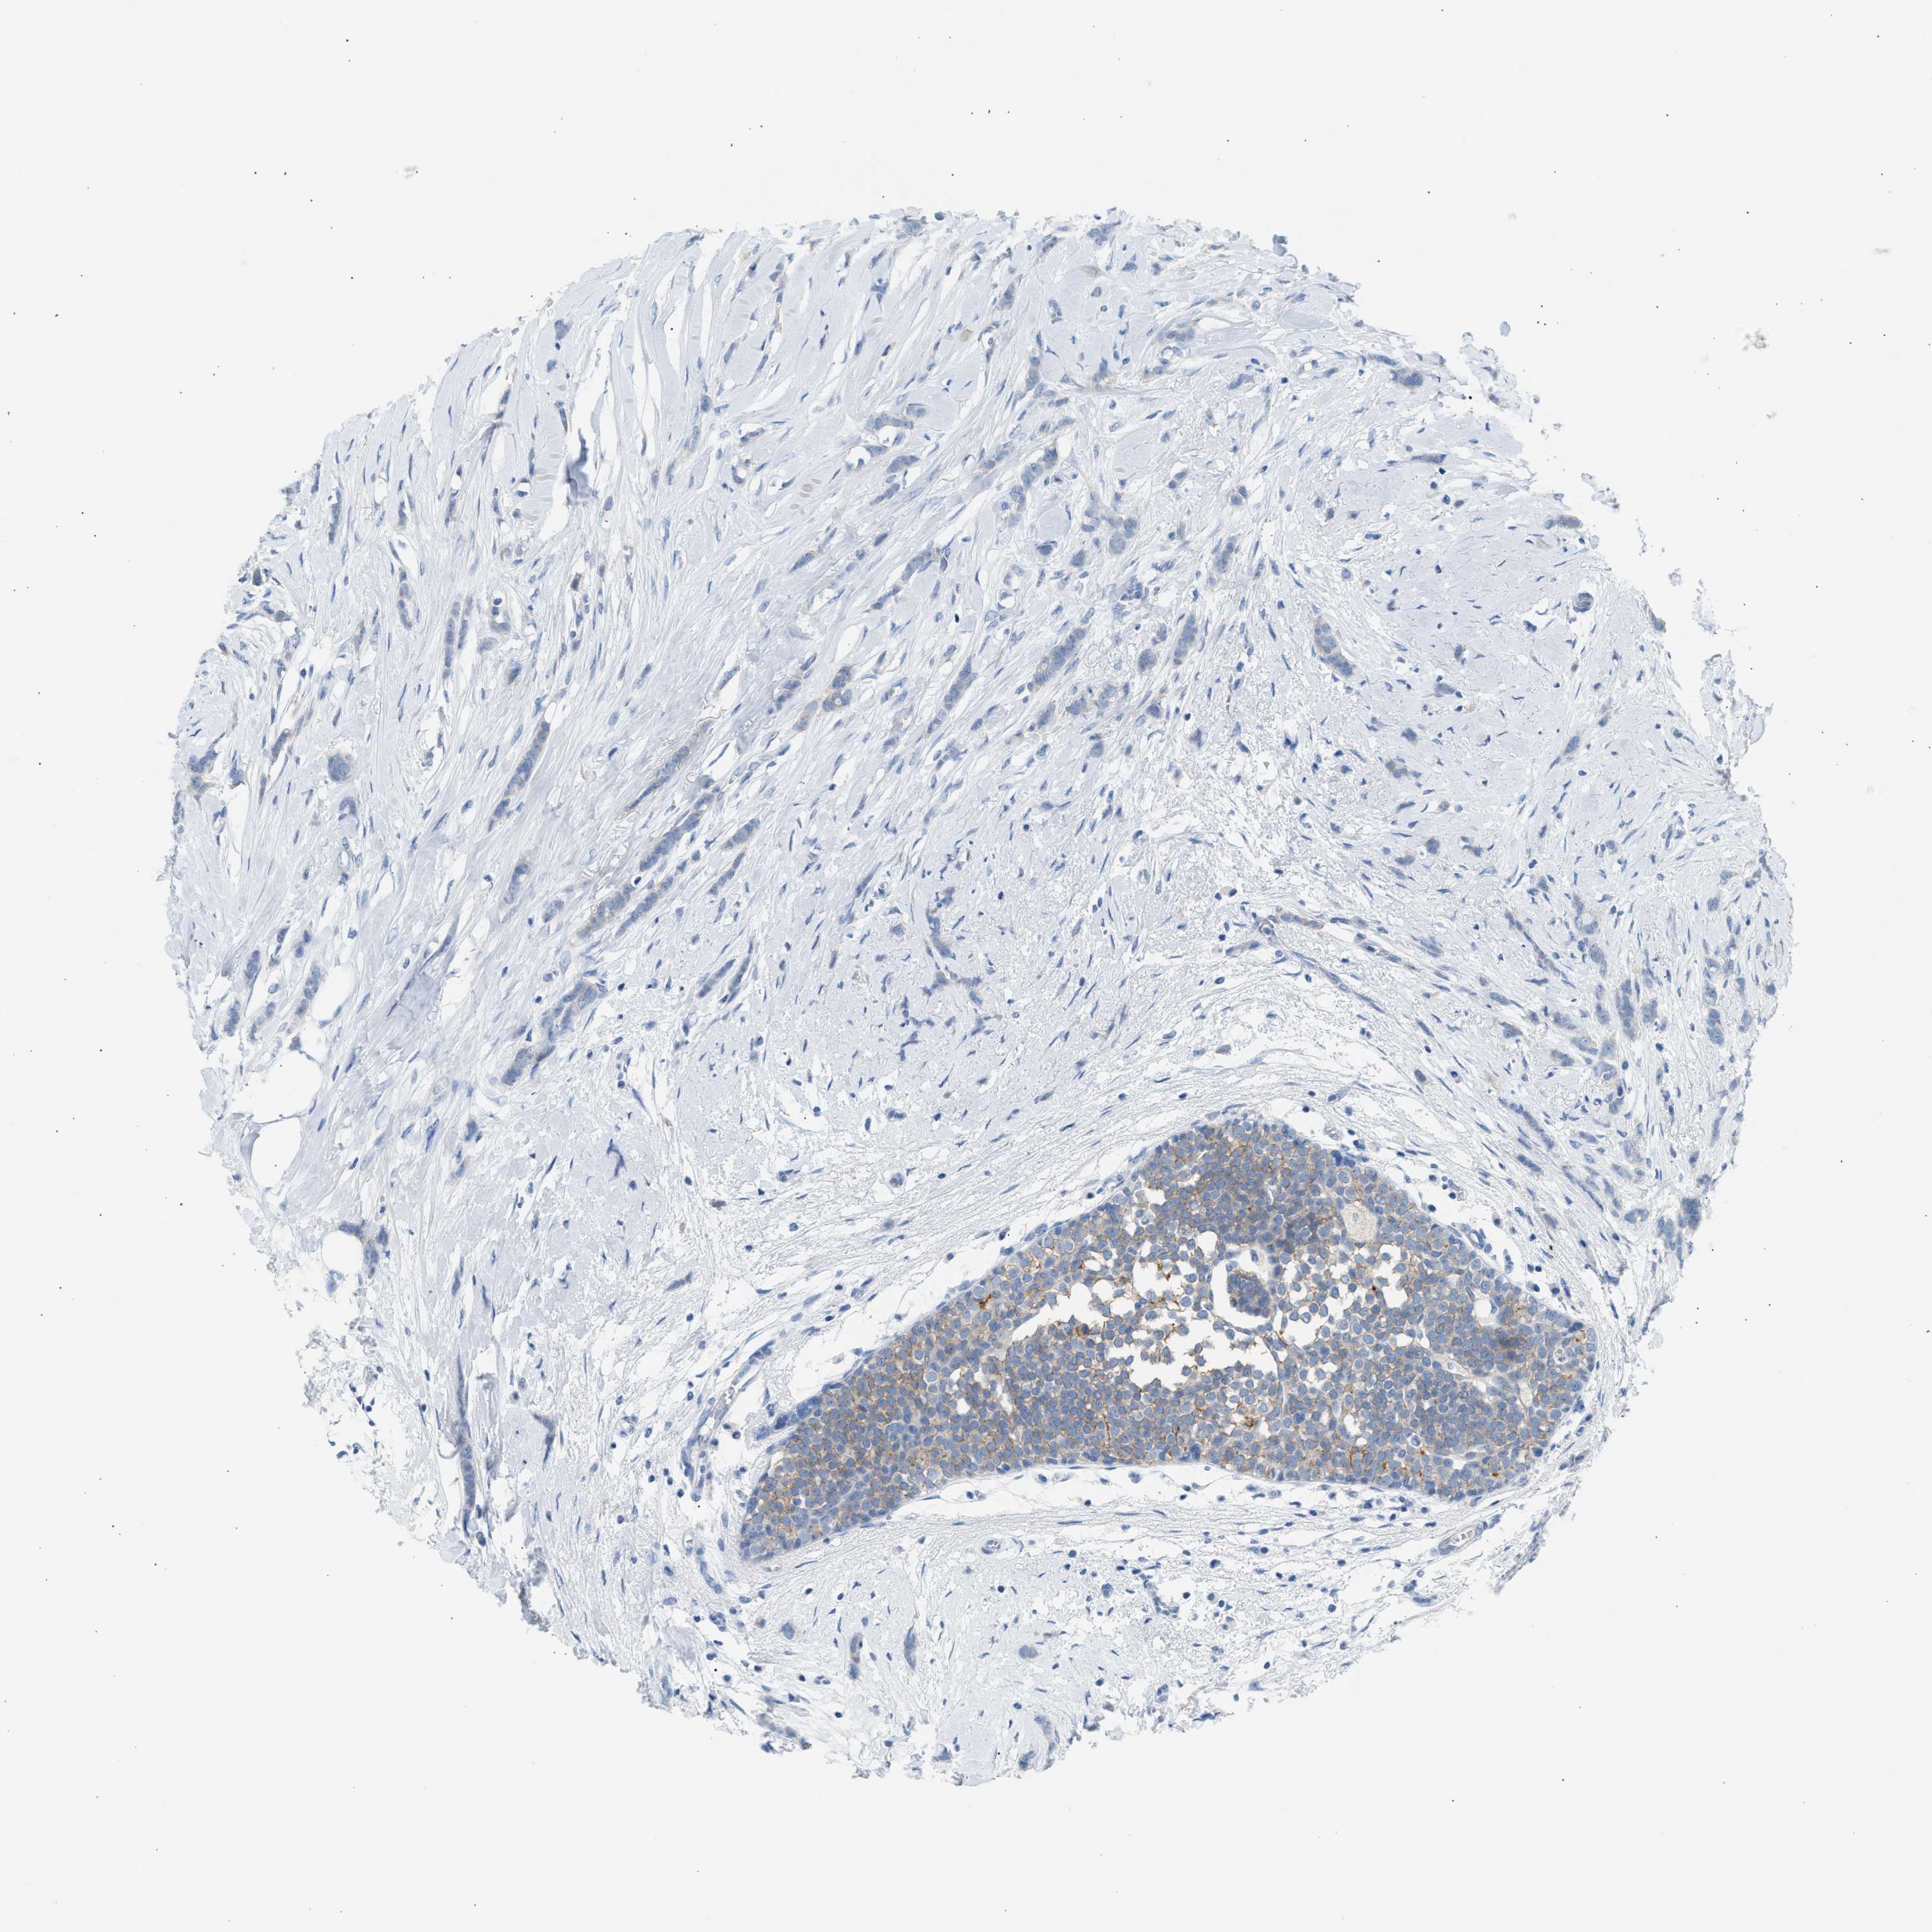

BRCA TCGA BRCA VALIDATION PROTEIN EXPRESSION

ANTIBODIES

AND

VALIDATION